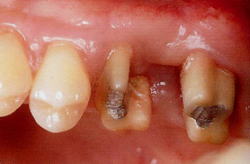

文献的にも、根分岐部の歯石は誰が、いかなる方法で取っても、取り残すことが証明されています。

| Matia, J.I.et al : Int.J.PRD 1986 | |